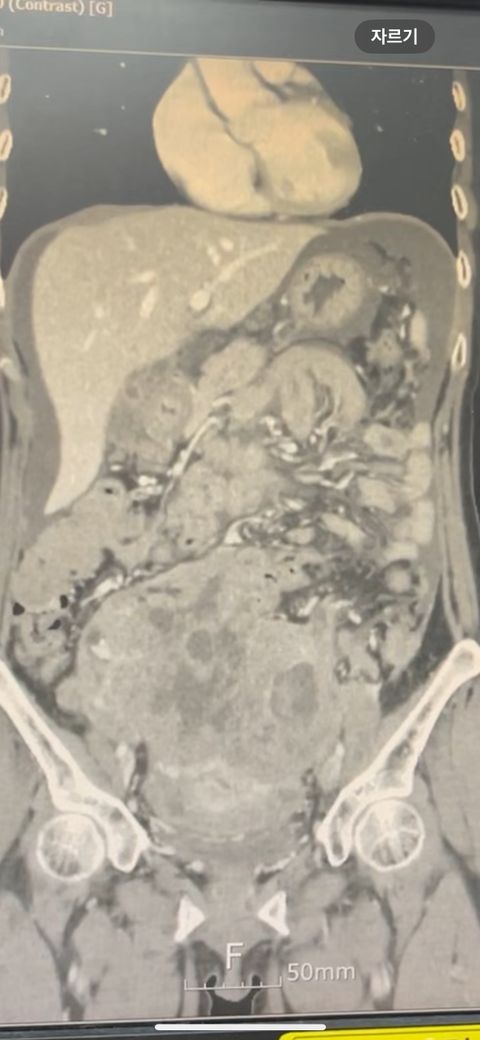

복부 ct 영상 판독부탁드립니다.!

결과는 3일 후 볼 예정인데 우선 영상만 받은 상태이고 너무 궁금한데 영상가지고 판독을 못해서요,,

이 사진가지고 확인할 수 있을까요 ?